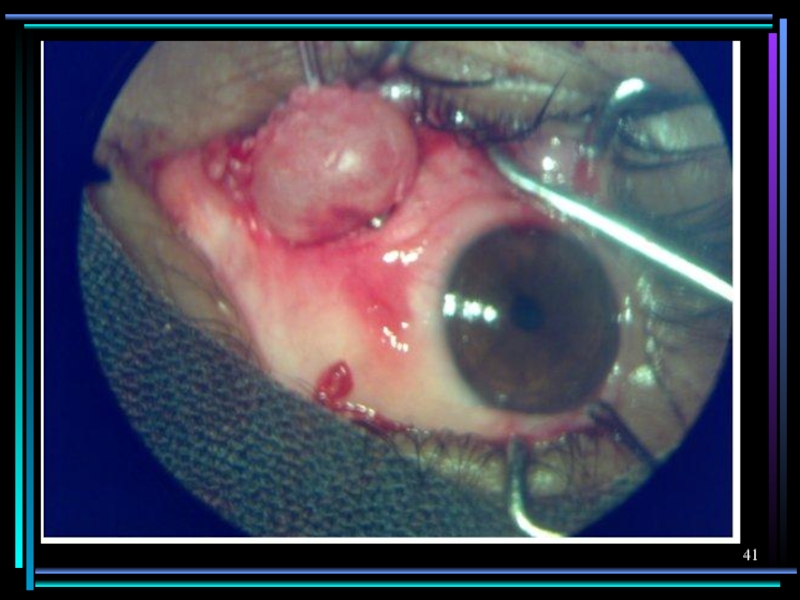

Слайд 39П о р а ж е н и е г

л а з

Цистицеркоз

Эхинококкоз

Локализация цистицерка под сетчаткой, отслойка сетчатки, перфорация стекловидного тела, воспалительная реакция после гибели гельминта

П о р а ж е н и е  г л а зЦистицеркозЭхинококкозЛокализация цистицерка под сетчаткой,